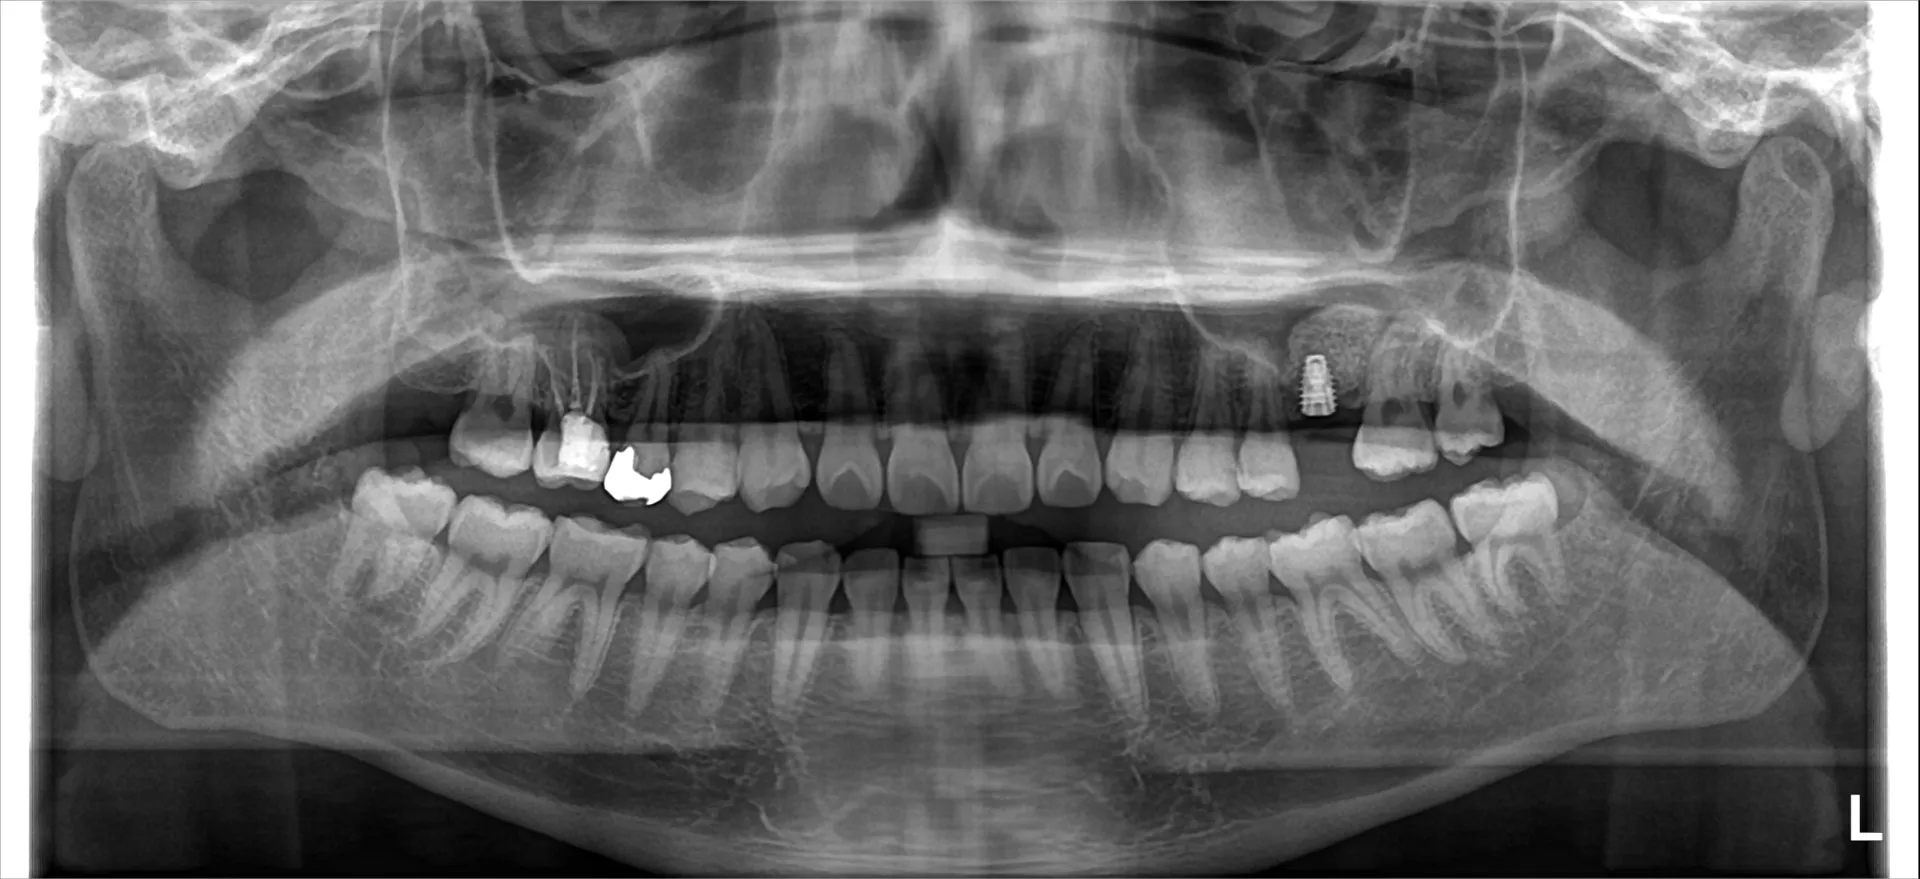

インプラントができない人 2025/11/10 こんにちは!千葉県市川市の妙典駅前にある妙典歯科Nクリニックです。 インプラントは多くの方に適用できますが、安全に手術できない・骨との結合が期待できないケースもあります。 「インプラントができ…

インプラントは外せるの? 2025/11/08 こんにちは!千葉県市川市の妙典駅前にある妙典歯科Nクリニックです。インプラントは基本的に撤去(除去)することが可能です。ただし、「撤去できる」=「簡単に外せる」という意味ではなく、状況によっ…

インプラント All onシステムって何? 2025/11/07 こんにちは!千葉県市川市の妙典駅前にある妙典歯科Nクリニックです。Allonシステムとは? 「All-on(オールオン)」は、歯がすべて失われた顎に、少数のインプラントで全体の人工歯を支える治療法です。…

総入れ歯か総インプラントか 2025/11/06 こんにちは!千葉県市川市の妙典駅前にある妙典歯科Nクリニックです。違いを比較歯が全て無くなった人の入れ歯を総入れ歯(総義歯)と呼びます。インプラントの場合はフルアーチインプラントです。 「フ…

親知らずが移植に使える?! 2025/11/05 こんにちは!千葉県市川市の妙典駅前にある妙典歯科Nクリニックです。親知らずと欠損部位 親知らず(智歯)は条件が合えば「歯の移植(自家歯牙移植)」に使えることがあります。 実際、歯を失った部位に…